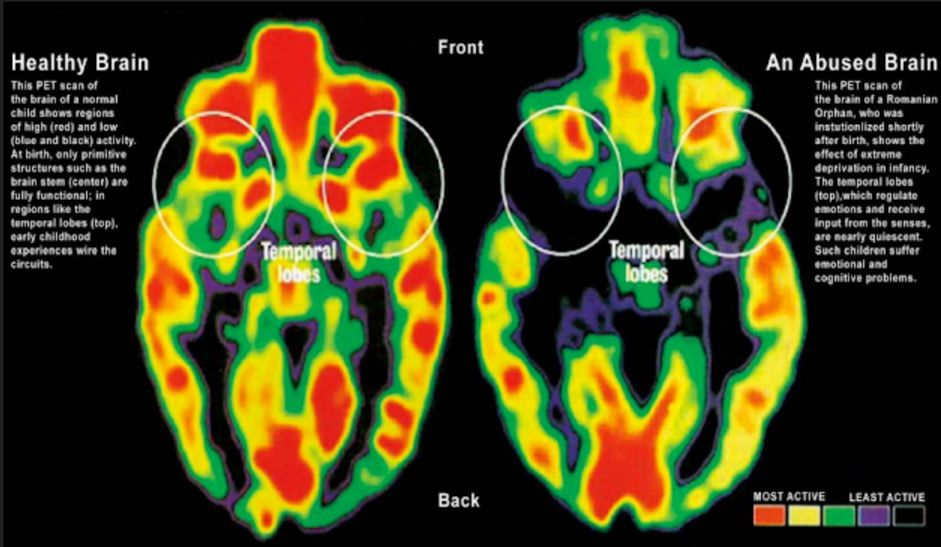

Deficyt w zakresie emocjonalnym może prowadzić w przyszłości m.in. do zaburzeń intelektualnych. Różnice jeszcze dobitniej widać, kiedy popatrzymy na skany mózgów z zaznaczeniem obszarów aktywnych i nieaktywnych. Kolor czerwony oznacza obszary najbardziej aktywne, czarny – te, które są w zaniku.

Powyższe skany jasno pokazują, że doświadczenia, które gromadzimy od pierwszych dni życia, determinują rozwój poszczególnych rejonów mózgu. Dziecko niekochane, opuszczone i zaniedbane nie rozwija się prawidłowo. W przyszłości może mieć problemy emocjonalne i poznawcze, które trudno będzie wyeliminować, bowiem niektóre sfery jego mózgu nigdy nie rozwinęły się prawidłowo.

U dzieci, które wychowywały się w domach dziecka zaobserwowano m.in. zaburzenia w rozwoju sfer odpowiedzialnych za koncentrację, myślenie analityczne i odczuwanie emocji.